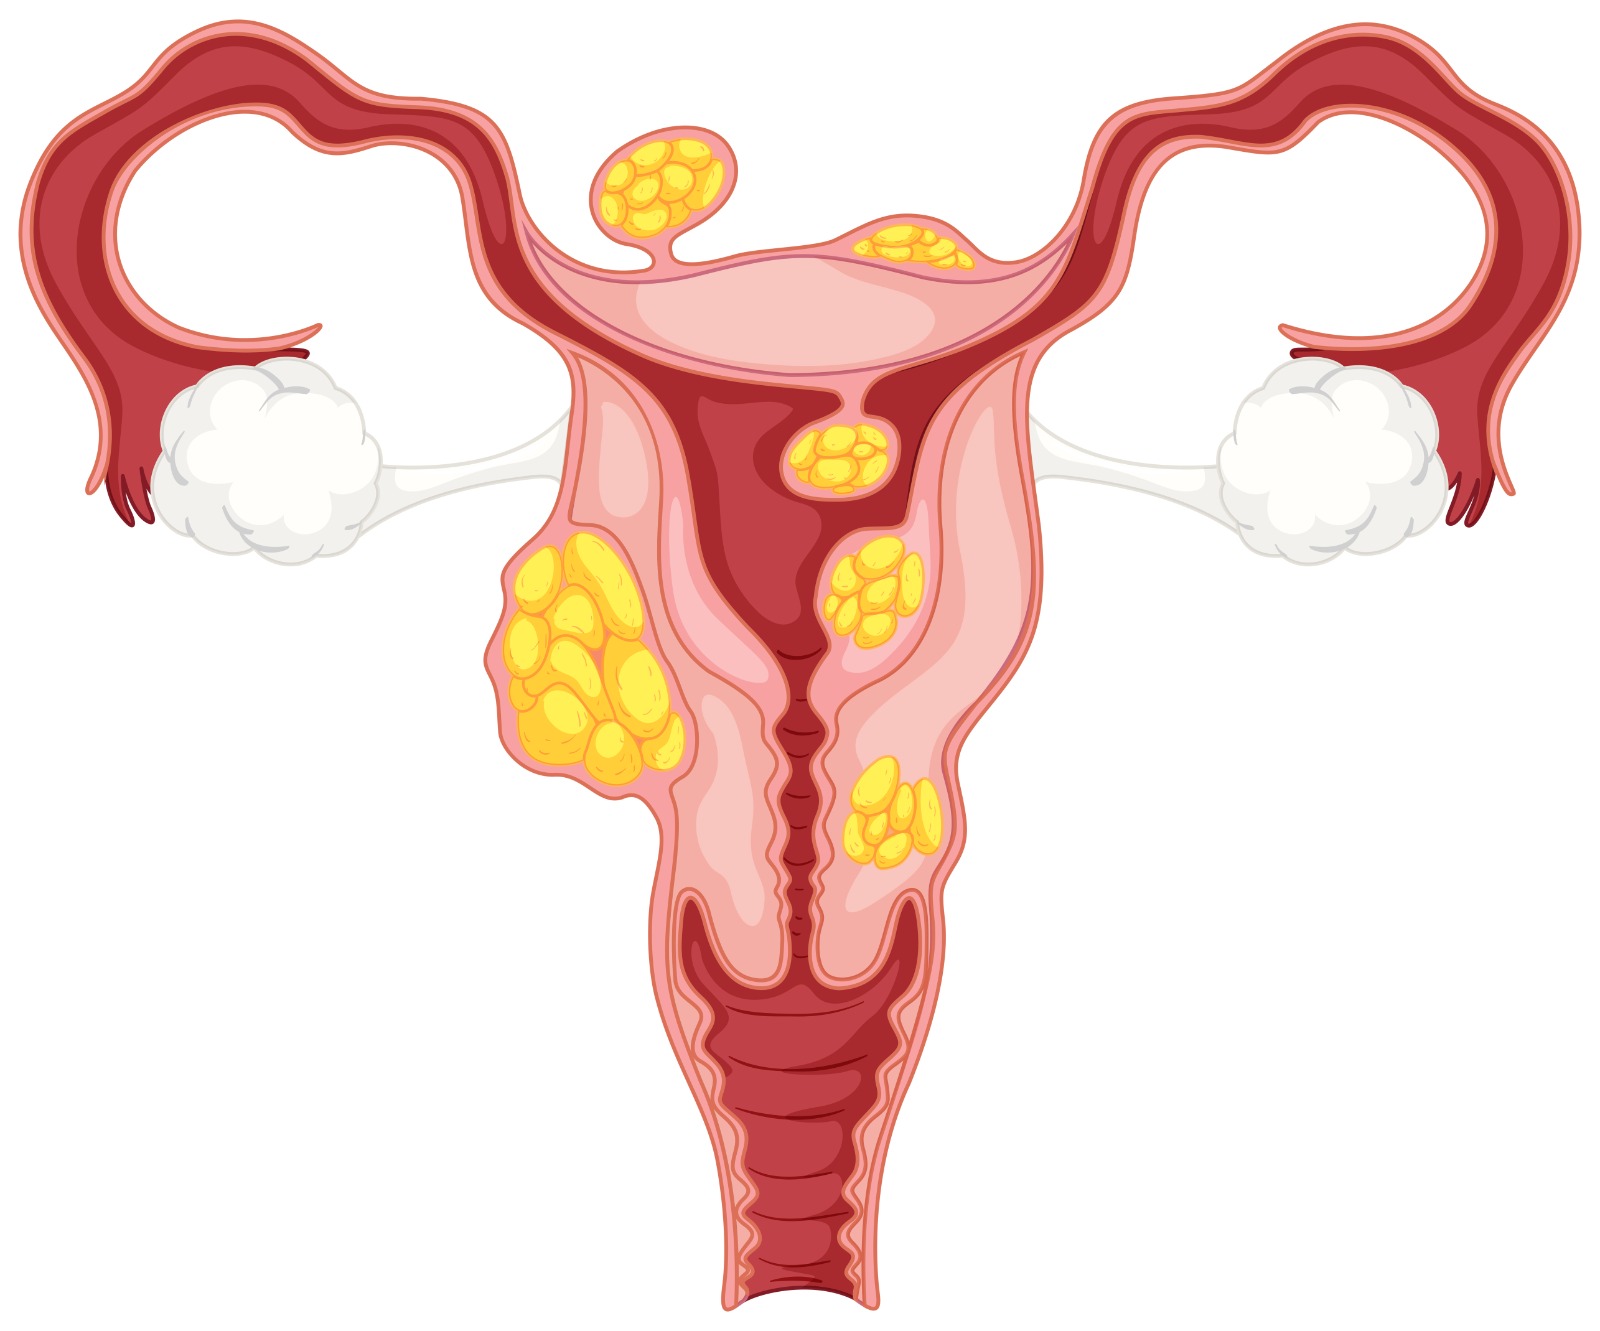

Uterine Fibroids (Leiomyomas) are non-cancerous growths that form in or around the uterus, arising from the smooth muscle tissue of the uterine wall. They are among the most common gynecological conditions in women of reproductive age. Common uterine fibroid symptoms include heavy menstrual bleeding, prolonged periods, pelvic pressure, frequent urination, and fertility difficulties.

There are several types of uterine fibroid, such as intramural, sub-serosal, submucosal, and pedunculated fibroids, each differing in location and impact. Accurate uterine fibroid diagnosis is made through pelvic examination, ultrasound, or MRI to determine size and number. Modern uterine fibroid treatment options include medication, minimally invasive procedures like Uterine Fibroid Embolization (UFE), and surgery when necessary. Preventive care through regular check-ups, hormonal balance, and maintaining a healthy lifestyle forms the basis of uterine fibroid prevention, supporting long-term reproductive wellness and symptom control.

Develop within the muscular wall of the uterus.

Forms just beneath the inner lining of the uterus.

Grows on the outer surface of the uterus, can press on nearby organs.

Attached by a stalk inside or outside the uterus.